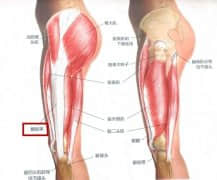

跑步膝盖痛,是髂胫束综合征?还是髌股关节综合征?